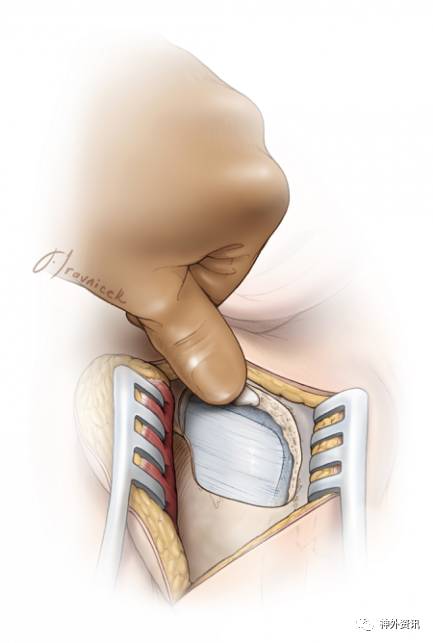

图11. 扩大乙状窦后入路:裸露后半部分乙状窦是该入路获得更大术野的关键步骤。

掀起骨瓣后,磨除部分乳突,显露乙状窦全长的后份。同时,去除外侧的乳突骨板和任何阻挡骨质使乙状窦可随硬膜往前翻转。因此,尽管可能对小脑的牵拉减轻了,但是从前外侧方观察桥小脑角的视野增加了,术者的操作角度也更灵活。